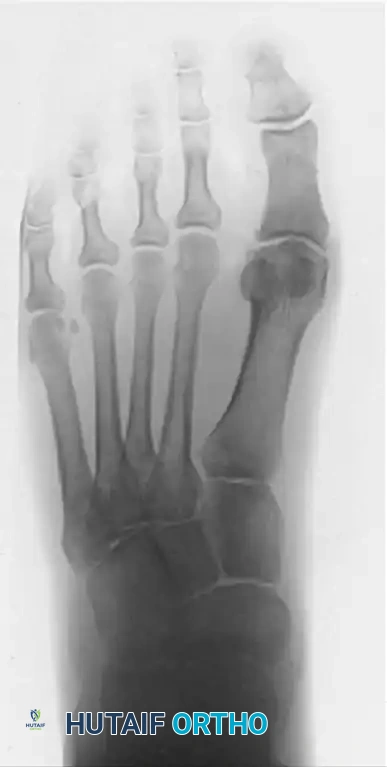

1 year post-op X-ray D

1 year post-op X-ray E

Figures 12-13: One year postoperative AP and Lateral radiographs demonstrating maintenance of the joint space, absence of recurrent osteophytes, and excellent preservation of the first ray architecture.